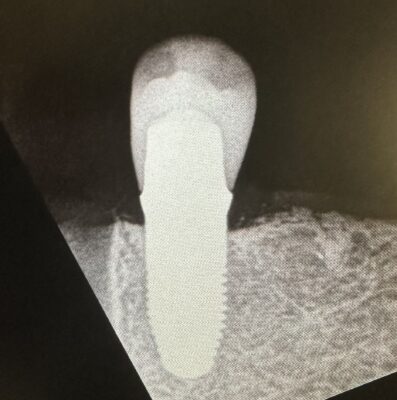

Hi, can someone please help me identify this implant please? Patient reports that she had the implant placed around 2007. Thank you!

Possible Implant Direct, or replace implant from Nobel. I would also recommend sending that information to your lab that sees lots and lots of different implants and they also could probably give you an idea what it is. I also find the website whatimplantisthat.com can be helpful as well